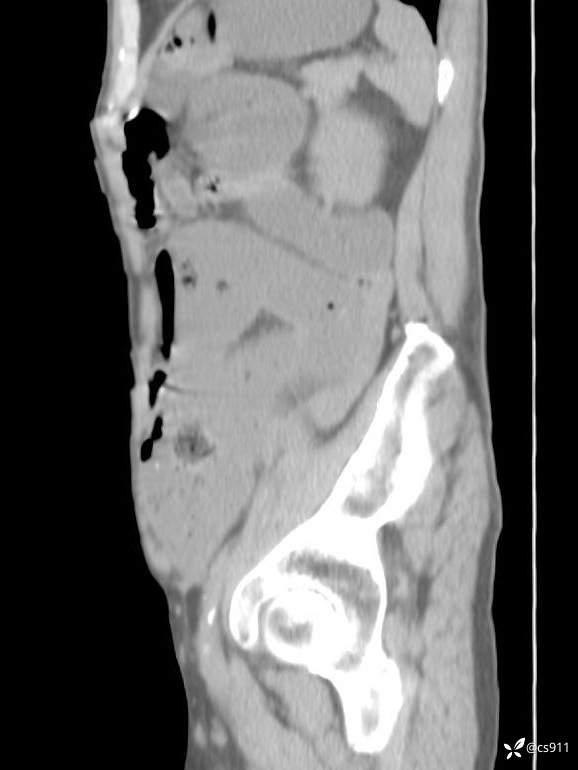

急腹症之急诊CT,原因?答案公布

男,77岁,腹痛、腹胀伴恶心呕吐1天。呕吐胃内容物,非喷射性呕吐,有咖啡色样胃内容物,诉有胃穿孔病史。查体:全腹平,下腹部压痛,全腹无反跳痛,叩诊呈浊音,移动性浊音阴性,肠鸣音减弱,1-2次/分。肛检:直肠未扪及明显肿物,可触及大量粪块。

T 36.6℃ P 80次/分 R 26次/分 BP 100/60mmHg

白细胞(WBC) H 14.55 10e9/L 4-10

红细胞(RBC) 4.58 10e12/L 4.3-5.8

中性粒细胞百分率(NEUT%) H 85.7 % 40-75

血淀粉酶(AMY) HH 1859 U/L 35-135

癌胚抗原(CEA) H 27.44 ng/ml 0-5

呕吐物 潜血试验 * 阳性 阴性

患者轮椅入室检查神志清楚, 能配合摆位和呼吸